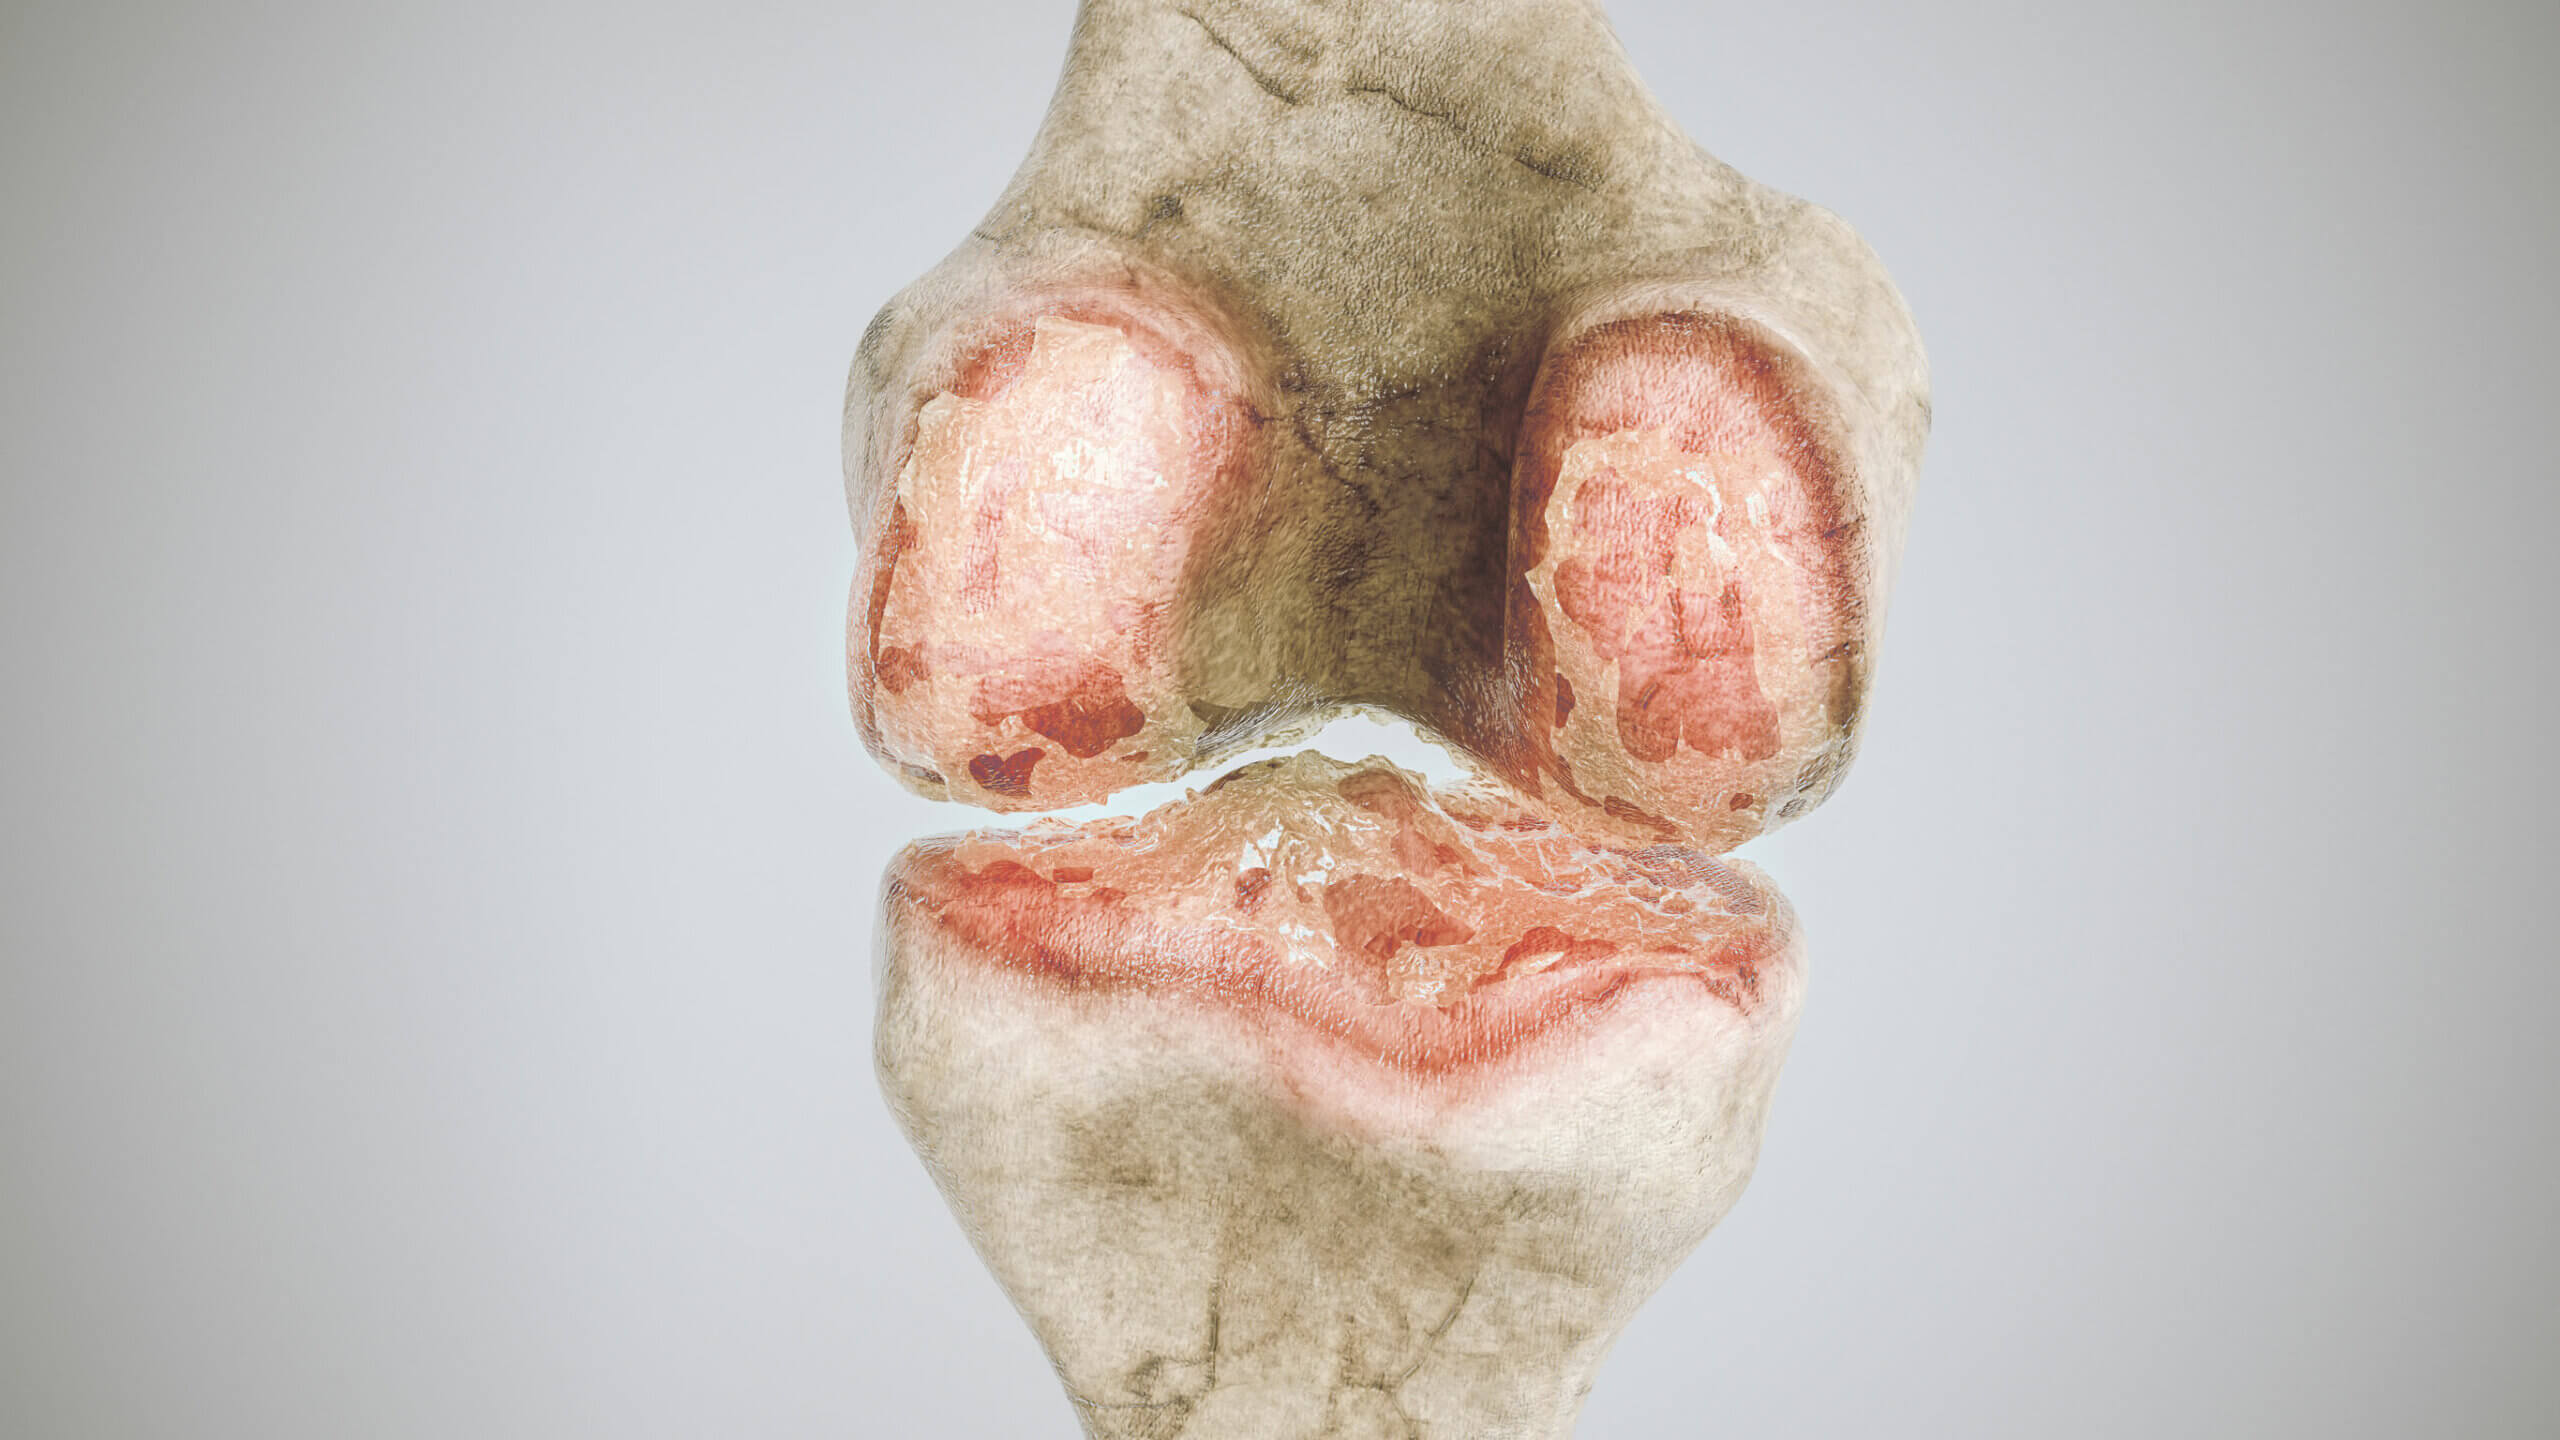

Artrosis

Se trata de una condición degenerativa de las articulaciones, cuya incidencia aumenta de forma considerable junto con la edad. Puede afectar a gran cantidad de articulaciones, sin importar el tamaño.

Desde un punto de vista clínico, el aspecto más resaltante es el dolor articular. Este puede acompañarse de rigidez y aumento de volumen ocasional.

A nivel radiológico, es posible evidenciar algunas estructuras llamadas osteofitos, unas protuberancias óseas que suelen desarrollarse en los extremos de los huesos.

A pesar de su componente degenerativo, también existe un proceso inflamatorio marcado que explica los síntomas. Por ello, muchos pacientes pueden verse beneficiados del tratamiento con antiinflamatorios no esteroideos, como el ibuprofeno.